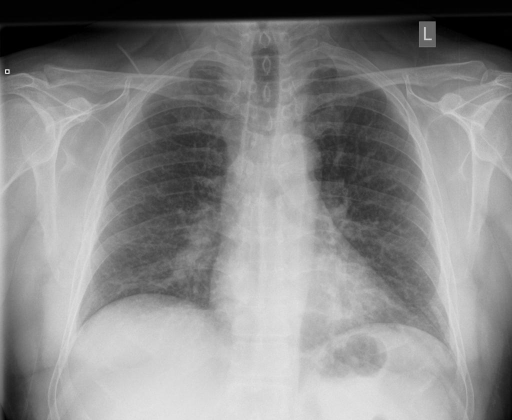

In Fig. 4, we show qualitative examples of the calculation of the cardio-thoracic-ratio for patients presenting cardiomegaly and not presenting cardiomegaly. For the case of the pathology, we see that the border of the heart is expanded, leading to a CTR above 0.7, whereas, for the absence case, the CTR is 0.4255.

When conducting a t-test, we get a value of 139.71 (p-value 0.0001) indicating a strong difference in CTR between positive and negative patients for cardiomegaly. We show this property in the violin plots on the left of Fig. 4, highlighting the CTR distributions for sex, age group, and pathology. Typically, the CTR for the presence and absence of cardiomegaly has noticeable shifts, with both respective means increasing with age. This average increase in CTR, however, becomes less in the age group of , with the disparity in mean CTR between cardiomegaly and no cardiomegaly reducing the older a patient gets. This result, in turn, lessens the insight of CTR with age. We observe this property for male and female patients. On the right of Fig. 4, we show the ROC-Curve for pathology classification based on the CTR score. We see a difference in the diagnostic performance of the CTR for female and male patients with an AuROC of 0.73 and 0.75.

In Fig. 4, we show qualitative examples of the calculation of the SCD for patients for the presence and absence of scoliosis. We can see that the vertebrae segmentation presents a noticeable curvature for the scoliosis case, leading to an SCD above 19, while for the patient with a healthy spine, the SCD is 1.125.

When conducting a t-test, we get a value of 35.30 (p-value 0.0001), indicating a statistically significant difference in SCD between positive and negative patients for scoliosis. On the left of Fig. 4, we show the distributions of the SCD in the form of violin plots for sex, age group, and pathology. Similarly to the CTR, SCD increases with age for the presence and absence of scoliosis. The results show that the older the patient gets, the less the disparity in mean SCD between scoliosis and no scoliosis becomes, indicating that the SCD becomes slightly less insightful the older the patient is. However, different from the CTR, the standard deviation of the SCD is considerably higher, and there is a relatively larger difference in means, leading to a higher predictive value for the identification of scoliosis.

On the right of Fig. 4, we show the ROC-Curve for pathology classification based on the SCD score. We see a difference in the diagnostic performance of the SCD for female and male patients with an AuROC of 0.77 and 0.80.